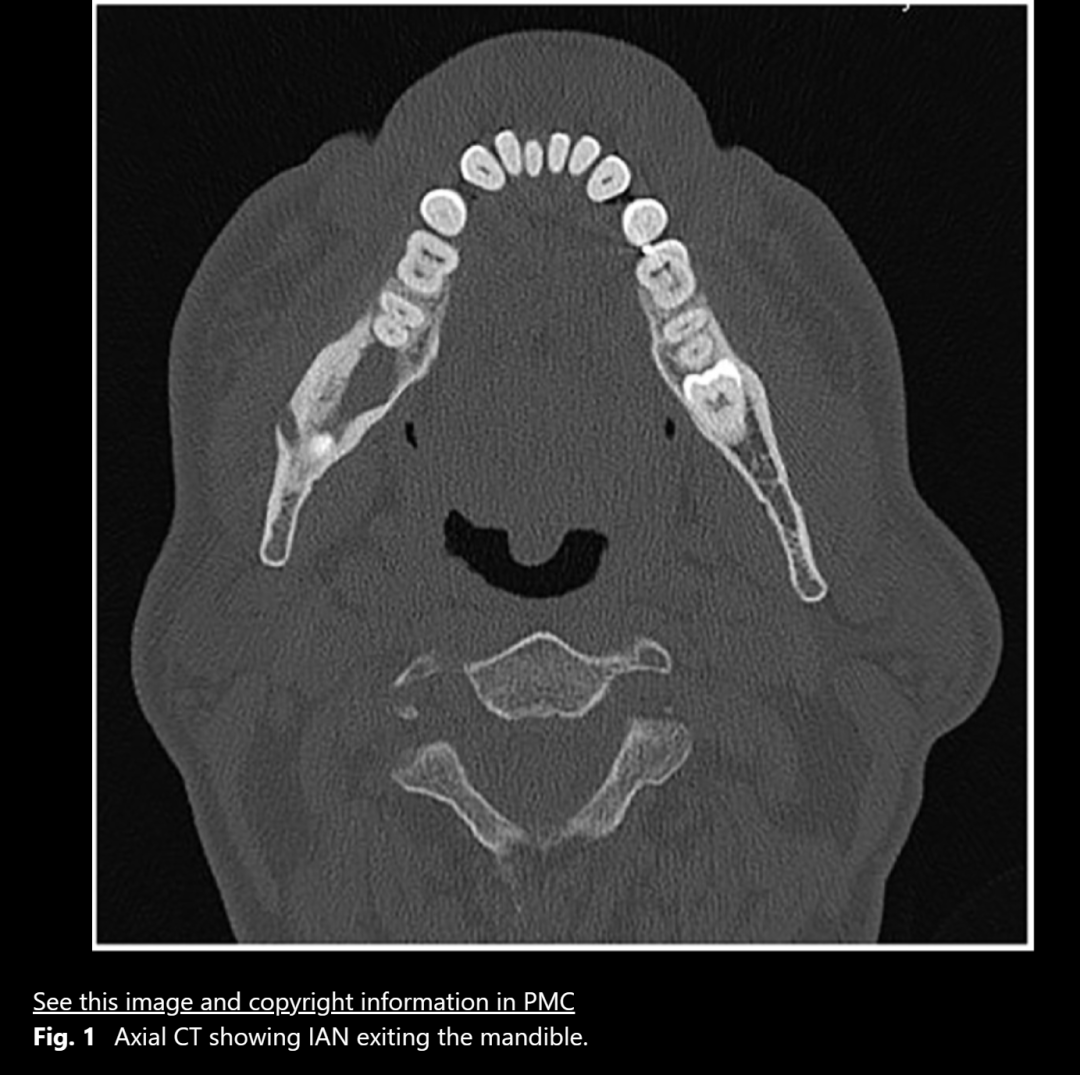

图1:下牙槽神经从下颌骨中穿出

在手术中进行翻瓣以暴露第三磨牙时,遇到了一些阻力。经过仔细检查,发现一根与骨膜瓣粘连的绳索状结构。将其轻轻分离后,确认该结构为下牙槽神经。该神经在距离口腔皮质骨外侧1.5厘米处穿出,且没有骨组织覆盖,随后重新进入下颌骨。

下牙槽神经被提起后,骨板上的凹槽显露出来。进一步对CT图像进行检查,确认下颌神经从颊侧骨板穿出,并且在神经与囊肿之间存在正常骨质,下颌神经在一个开放的通道内自由移动。